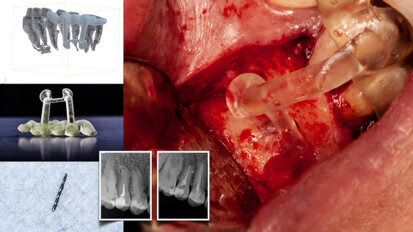

Management of iatrogenic pulpal floor perforation in a mandibular molar with MTA and PRF

This was a challenging case with the combined issues of a failed root canal therapy and an iatrogenic perforation of the floor of the pulp chamber. Though ...

How CAD/CAM affects immediate loading in implant dentistry

A graduate of Paris Descartes University (now the University of Paris), Dr Léon Pariente currently runs a private practice in the French capital that ...